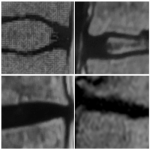

INSTRUCCIÓN ORTOPÉDICA DE POSGRADO – IMÁGENES

Presentación del caso

Pedro L. Bazán, Arles Pérez Gutiérrez, Alin L. Garay

Resolución del caso